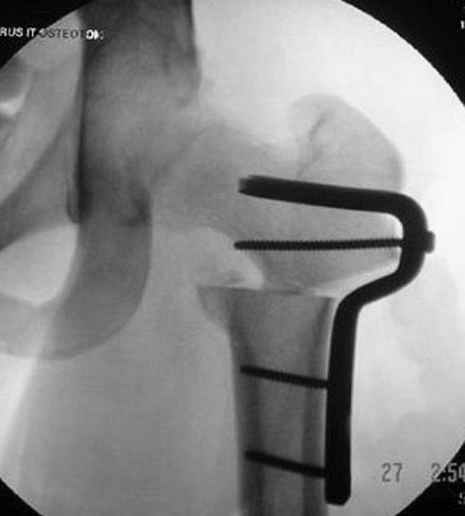

Отправитель: Alexander Chelnokov 23 Ноябрь 2004, 02:31

Если, например, доводится лечить больных с псевдартрозами шейки бедра, то надобность есть, и приходится. См. приложение.

Несколько снимков из моей коллекции, чтобы разьяснить, почему мы до сих пор делаем различные варианты остеотомии.

На рисунке N1 предоперационный план лечения ложного сустава шейки бедра- линия ложного сустава, угол и направление введения импланта, клиновидная остеотомия в градусах и миллиметрах, второй снимок после коррекции, расчет, на сколько удлиняется конечность и размеры импланта;

N3 рисунок окончательный снимок, после операции моя рентгенограмма должен выглядеть примерно как эта картина. На N4 снимке клин перед удалением; N5 послеоперации 3 нед.; N6 окончательная рентгенограмма.